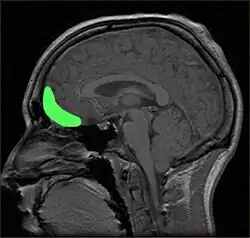

L'impulsivité est un comportement présent dans de nombreux troubles neuropsychiatriques incluant trouble du déficit de l'attention, trouble bipolaire, trouble du spectre de l'alcoolisation fœtale, trouble de la personnalité antisociale, trouble de la personnalité borderline et trouble de la personnalité histrionique et certaines causes de dépression et suicide[9],[10]. Des niveaux anormaux de traits impulsifs peuvent être causés par des maladies neurodégénératives, un traumatisme crânien, des infections virales ou bactériennes ou neurotoxicité à la suite de l'exposition de produits chimiques. Certains traumatismes ou anomalies du cortex orbitofrontal et le gyrus frontal inférieur provoquent les traits de l'impulsivité[11],[12],[13], bien que certaines connexions cérébrales peuvent contribuer à de différentes manifestations de l'impulsivité[14].